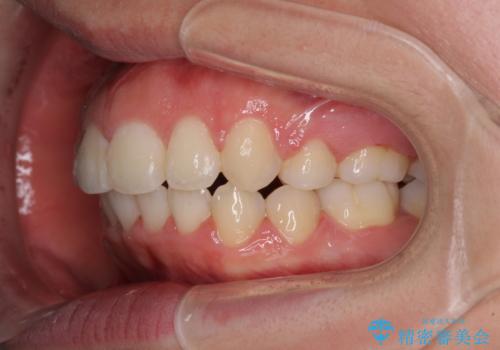

著しい叢生と顎骨のズレ ワイヤー装置による抜歯矯正

- 前歯の著しい叢生や八重歯を気にして来院された患者様です。

上下の顎がずれており、上下の正中は歯1本分の差がありました。

咬み合わせの乱れが著しく、治療途中で一部反対咬合となってしまいました。

アンカーなどをうまく使用して、3年の期間を要してきれいに仕上げることができました。